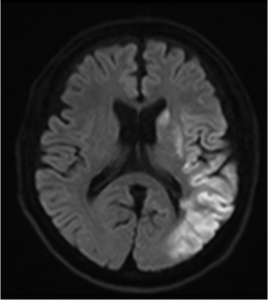

脳梗塞の症状は詰まった血管の場所や太さによって症状が異なるため様々です。脳の太い血管が詰まる重症の脳梗塞では手足は完全に麻痺してしまい、左右どちらかの一点を見つめ、意識が悪くなり呼吸がおかしくなったりします。一方で、ラクナ梗塞などの細い血管のみが詰まって起こる脳梗塞では少し呂律が回らないなど、日常生活が行えるくらい軽症なこともあります。軽症の脳梗塞であっても、脳梗塞は発症してすぐは再発や症状が悪くなる危険性が高く治療や再発予防が必要です。非常に早期の小さな脳梗塞でもMRI検査で見つけられるケースが増えていますので、「脳梗塞かも?」という症状があれば受診してください。

| ラクナ梗塞 | 最も多い脳梗塞のタイプです。脳の中の細い血管が詰まって起こる1.5cm以下の小さな脳梗塞です。軽い麻痺や感覚障害が出ることが多いです。気づかないうちにラクナ梗塞を起こしていることもあります(無症候性脳梗塞)。高血圧や糖尿病などが生活習慣病が原因となります。 |

脳出血の最大の危険因子は高血圧であり、長年にわたる高血圧によって細い脳血管の壁がもろくなり破れやすくなることが主な原因です。また、MRI検査で「脳微小出血(小さな出血の痕)」が認められることがあり、これは脳血管の弱い部分で起きたごく小さな出血です。脳微小出血があると、将来の脳出血のリスクが高まる可能性があると考えられています。